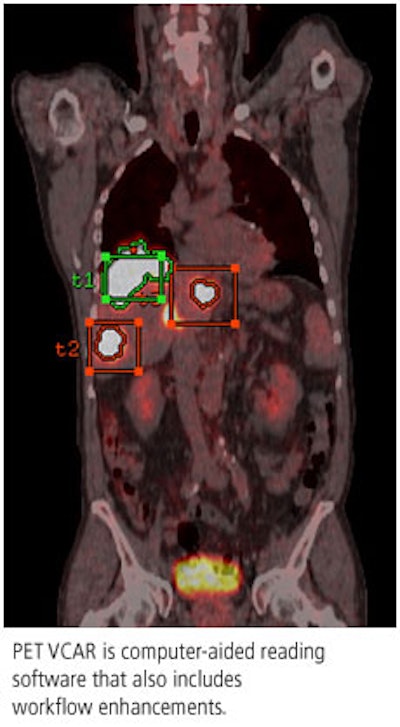

PET VCAR is designed for helping clinicians diagnose, stage, and treat lesions by identifying and tracking areas of metabolic activity on PET/CT scans, and the software also includes registration features for comparing tumor response over time. PET VCAR received 510(k) clearance from the U.S. Food and Drug Administration (FDA) in March 2007.